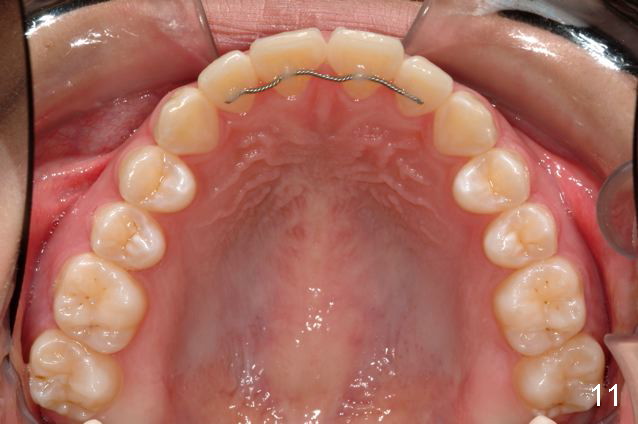

Why do the upper incisors need a lingual retainer?

Answer: I was afraid tooth #8 would try to rotate (Fig.).  I do not like U bonded retainers as much as lower but I thought maybe in this case due to #8 initial position.  I have provided 2 removable retainers to fit over for insurance!